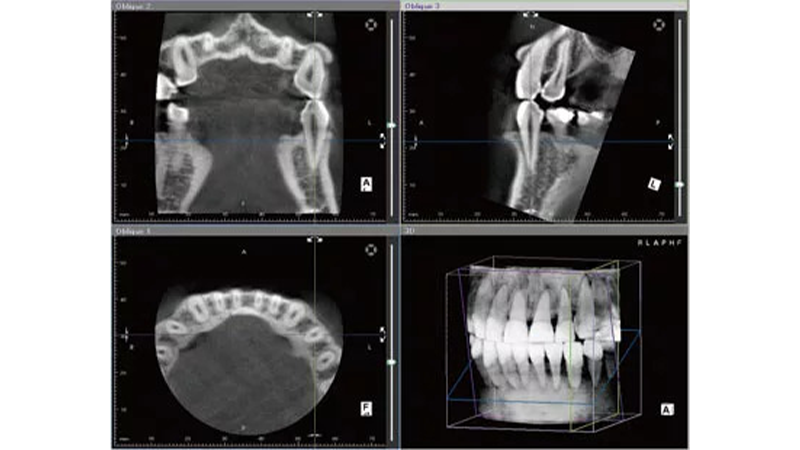

- 歯科用CT:顎の骨や神経・血管の位置を3Dで把握

- サージカルガイド:理想的な位置・角度・深さを正確に誘導

- 専用オペ室:生体監視モニター・滅菌設備・口腔外バキューム完備

治療は“科学と精密”の上に成り立っています。

感覚や勘ではなく、数値とデータに基づいた安全な医療を提供しています。

一人ひとりの骨の形や厚みをCTで精密に解析し、